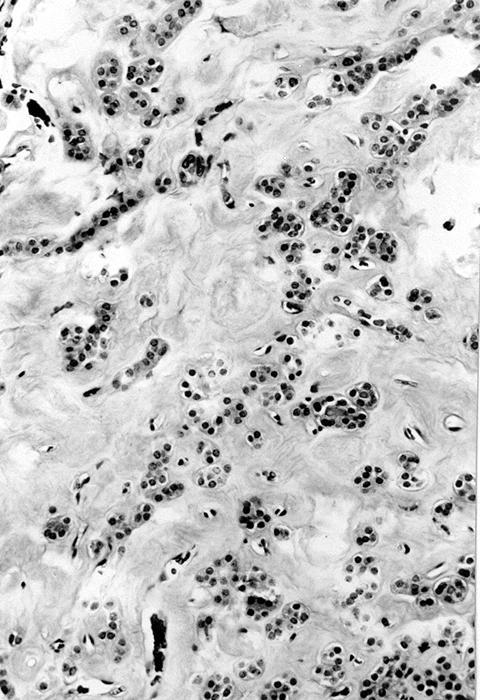

Microscopic (histologic) images

Contributed by Shipra Agarwal, M.D., Andrey Bychkov, M.D., Ph.D., Mark R. Wick, M.D., Asmaa Gaber Abdou, M.D. and AFIP

Atypical adenomas:

- Variants

- Hyperfunctioning adenoma (Plummer adenoma): tall columnar epithelium, papillary infoldings, vacuolated cytoplasm, watery colloid showing scalloping

- Follicular adenoma with papillary hyperplasia: cystically dilated follicles, intraluminal papillae

- Lipoadenoma: adipocytic metaplasia of the follicular adenoma

- Follicular adenoma with bizarre nuclei: may be seen after radiation exposure and in hyperfunctioning adenoma

- Signet ring cell follicular adenoma: signet ring cell change

- Clear cell follicular adenoma: follicular adenoma with clear cell change

- Spindle cell follicular adenoma: spindle cell metaplasia

- Black follicular adenoma (black pigment in tumor cell cytoplasm; in patients on minocycline therapy)